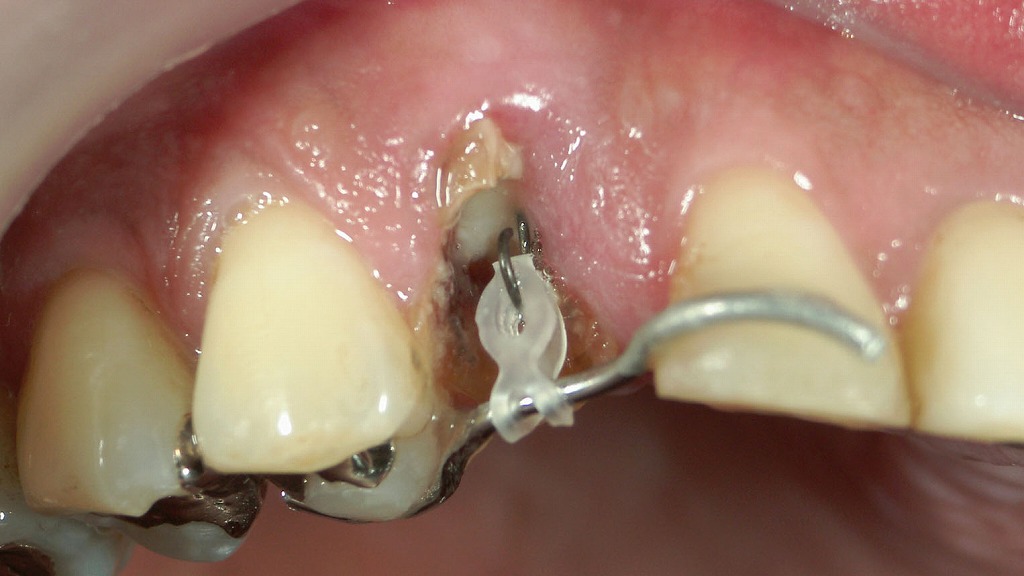

抜歯後の補綴治療|上顎6番相当部におけるインプラント治療の流れ

上顎6番を抜歯後、欠損部の機能回復を目的としてインプラント治療を行った症例です。1枚目はインプラント埋入手術時の口腔内写真、2枚目は最終的にインプラント上部構造を装着した後のX線画像を示しています。適切な位置と角度でインプラントを埋入することで、周囲骨との良好な適合が得られ、咬合力を安定して支えられる状態となっています。隣在歯を削る必要がなく、見た目と噛む機能の両立を図れる点が、抜歯後の補綴治療としてのインプラントの大きな特長です。